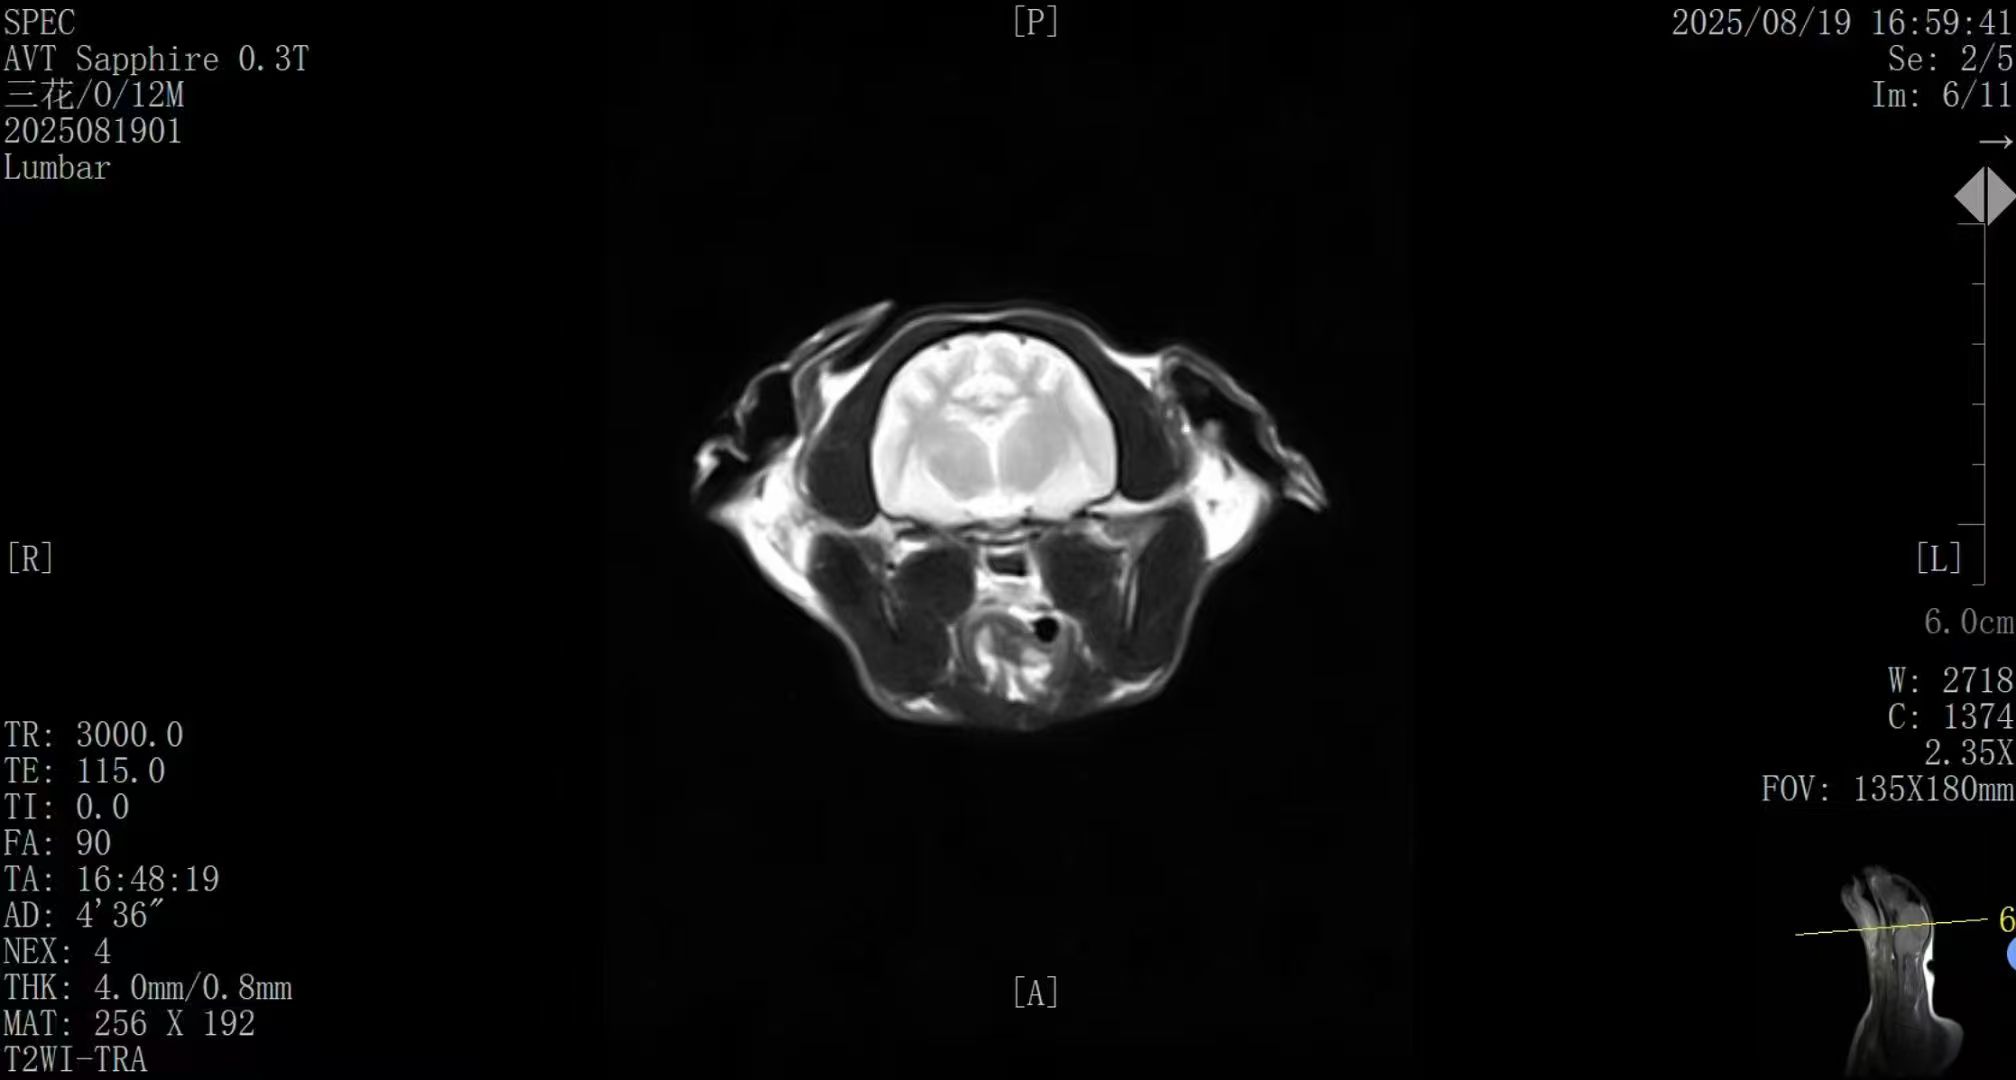

专科化诊疗离不开精准的影像诊断支持。在神经系统疾病、软组织损伤及早期肿瘤筛查方面,磁共振成像(MRI)具有不可替代的优势。它无辐射伤害,能实现多角度高清扫描,被誉为诊断软组织疾病的“金标准”。

02:其次是 “智能化”驱动的诊断升级。设备集成新一代AI影像优化系统,能对图像进行深度学习和实时重建。

官方验证数据显示,其图像信噪比与软组织对比度可获得显著提升,在神经、脊柱、关节等关键部位的成像清晰度达到诊断级标准,完全能满足专科诊疗的精准需求。